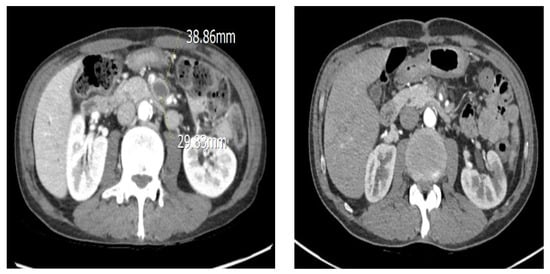

6.4. The Patient Was Diagnosed with SMA Aneurysm Using Abdominal CT, Which Was Followed by Persistent Abdominal Pain and Fever—Surgery Was Performed on the Transplanted Vessel